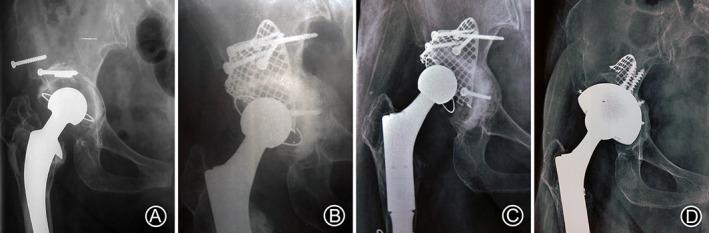

In revision total hip arthroplasty (THA), reconstruction of severe acetabular bone defect continues to be problematic for orthopedic surgeons. This study reports the mid- to long-term survivorship, radiological outcomes, and complications of impaction bone grafting (IBG) and metal mesh with a cemented acetabular component in the reconstruction of severe acetabular bone defects in revision THA.

This retrospective consecutive study included 26 patients (29 hips: type II B, four; type II C, three; type III A, 10; and type III B, 12) who underwent revision THA, which was performed using IBG and metal mesh, between 2007 and 2014 in our institution. All patients were followed up regularly for clinical and radiographical assessments. Migration and loosening of prosthesis graft integration and complications were observed and analyzed. Survival analysis was performed using a Kaplan-Meier survival analysis.

At the time of revision, 75.9% of the hips (22 hips) were classified as type III bone defects. The average follow-up period was 9.4 ± 2.8 (range, 2.4-14.0) years. Of the 29 hips, four hips (13.8%) were assessed as clinical failures; at the last follow-up, two had undergone re-revision THA, and two had not been scheduled for re-revision THA despite radiological failure of the acetabular component. Among them, three clinical failures (10.3%) were due to aseptic loosening, and one (3.4%) was due to infection. Radiographic evaluation showed bone graft integration in all hips during the follow-up. The Kaplan-Meier survivorship analysis revealed an acetabular reconstruction survival rate of 86.5% (95% confidence interval, 61.4%-95.7%) at 10 years.

IBG and metal mesh with a cemented acetabular component for revision THA is an effective technique for treating severe acetabular bone defects, with effective mid- to long-term outcomes due to the solid reconstruction of the acetabular bone defect and restoration of the hip rotation center.